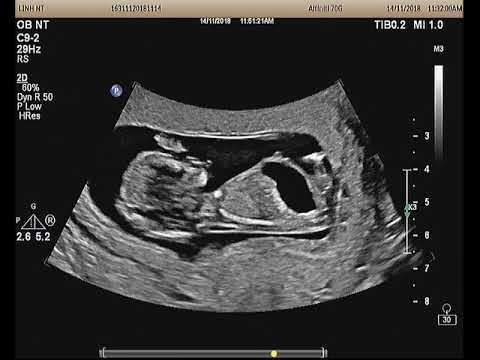

Siêu âm thai 13 tuần: bàng quang lớn, nang dây rốn, dây rốn 1 động mạch